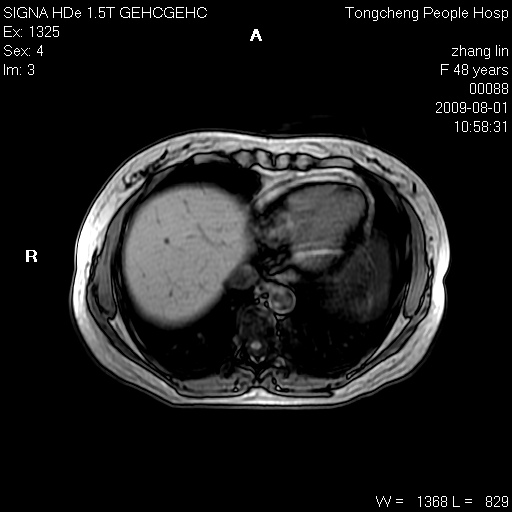

女,48岁。健康体检,彩超发现右肾占位性病变。平素健康。

临床诊断:右肾占位性病变,性质待定(囊肿?肿瘤?)。

上中腹部mr平扫+增强扫描,图像如下:

右肾上极见一类圆形病灶,t1wi呈等信号t2wi呈等高混杂信号,三期增强无强化,边界清---考虑囊肿出血。

同反相位均表现为等信号,病变无强化,考虑含蛋白的囊肿可能,弥散加权相或许有些帮助,

肝囊肿